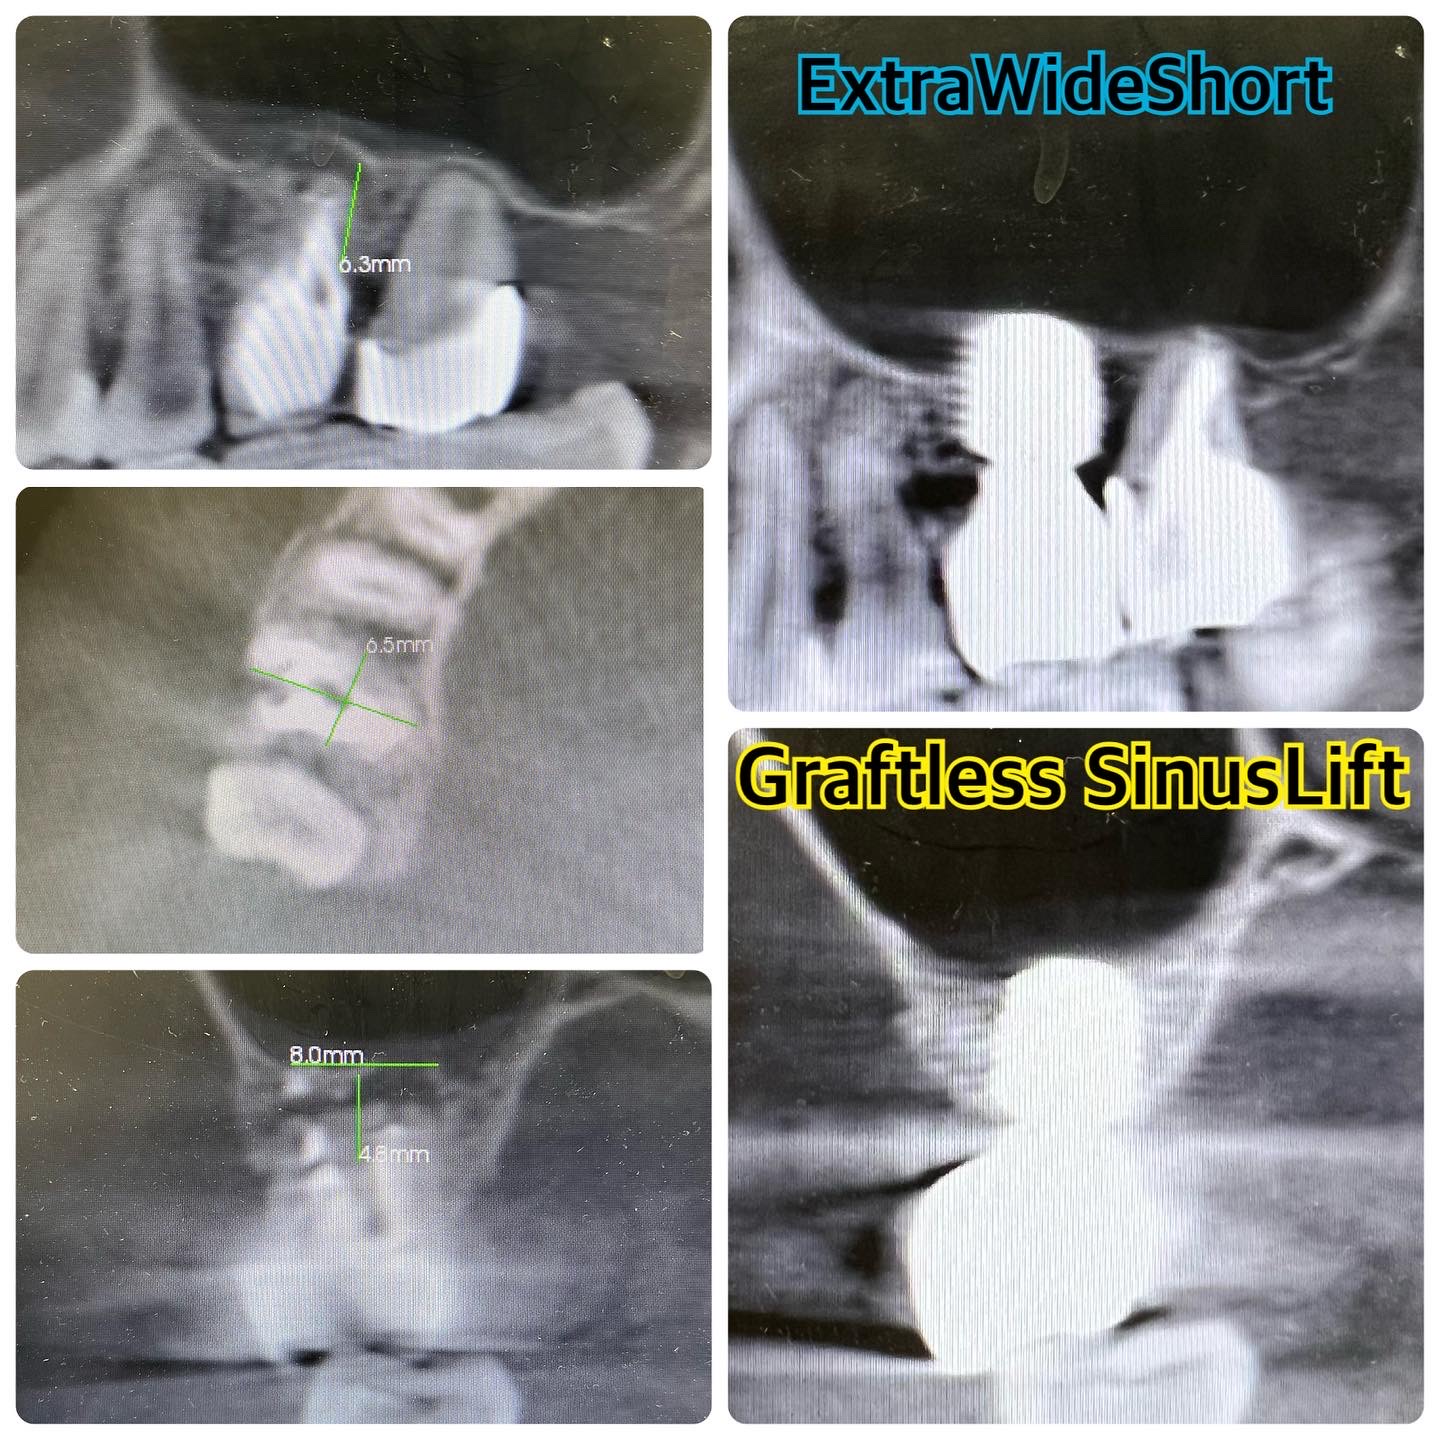

レントゲン撮影すると、ExtraWideShortImplantの周囲やに骨が出来ており、先端にはスロープ状に骨ができていることが確認できます。まさにこのような症例にしたくて勉強しているので、仕上がりとしてはとても嬉しいです。さらに勉強を続けてより規格性の高いインプラント治療をしていきたいです。